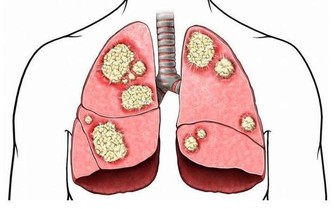

如果雙手是能一窺健康的門戶,那位於手足之端、也就是經脈終始點的井穴,就是身體與外界溝通的窗口。《黃帝內經。靈樞》將井穴喻為水之源頭,是精氣所出的部位,對於調節臟腑、氣血、經脈之氣有相當重要的作用。裡頭也提到,「病在臟者取之井」。顯見,透過井穴,可以治療相應臟腑的疾病。

循著連接手指的六條經絡及其相應經氣,大拇指的少商穴對應肺、脾食指的商陽穴對應大腸、胃中指的中沖穴對應心包、肝無名指的關沖穴對應三焦、膽小指的少澤穴對應心、腎少沖穴對應小腸、膀胱。

井穴有清熱、醒腦、安神的作用,平時醫師會藉由放血、針灸達到治療效果,中醫則建議,一般民眾平時可以透過井穴按摩來保養身體,精神不濟時,開過十指井穴也能活絡臟腑、重拾元氣。